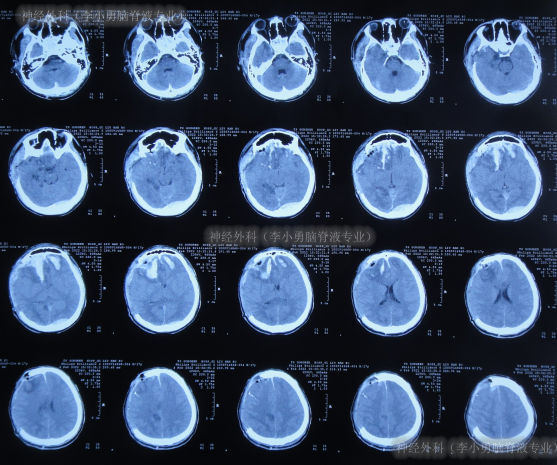

入院时头颅CT示颅骨修补术后,脑分流术后仍脑积水(图-17)。

图-17:2022年6月9日头颅CT

入院后次日即2022年6月10日,拔除了原脑室腹腔分流管+脑室外引流术(图-18)。

图-18:2022年6月10日头颅CT

住院18天即2022年6月27日,进行了脑室腹壁外引流术(图-21)。

图-21:2022年6月27日头颅CT

住院54天即2022年8月2日,头颅CT示脑室进一步缩小(图-25)。

图-25:2022年8月2日头颅CT

住院65天即2022年8月13日,查头颅CT示脑室变小,颅内感染也进一步减轻(图-26)。

图-26:2022年8月13日头颅CT

住院111天即2022年9月28日,病情进一步好转为:意识清楚,言语交流正常,饮食变正常,右侧肢体活动正常,左侧肢体活动差些(图-27);头颅CT示引流术后状态,未见异常(图-28)。

图-27:2022年9月28 日

图-28:2022年9月29日头颅CT

待脑脊液各项化验达标后于2022年10月8日,进行了脑室腹腔分流术(图-29)。

图-29:2022年10月8日头颅CT